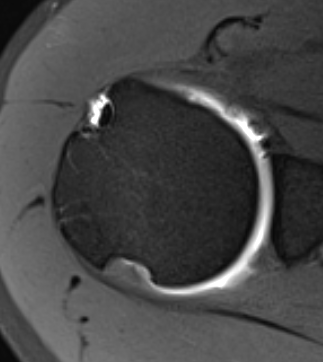

Measurement Hill Sachs

Best fit circle of the articular surface of humeral head

Measure percentage involvement of articular surface

Hill Sachs 30% of the articular surface

Hill Sachs 25% of the articular surface